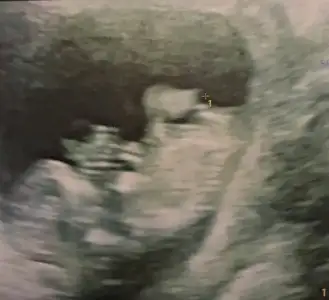

erkekmiş kesin, 1 hafta büyük görünüyor yani 13+0 böyle olunca doğum tarihi 29 haziran görünüyor

İki gün önce de net görünüyordu ama ikili testte daha net görünür demişti baya net pipi var

İki gün önce de net görünüyordu ama ikili testte daha net görünür demişti baya net pipi var[/QUOTE]